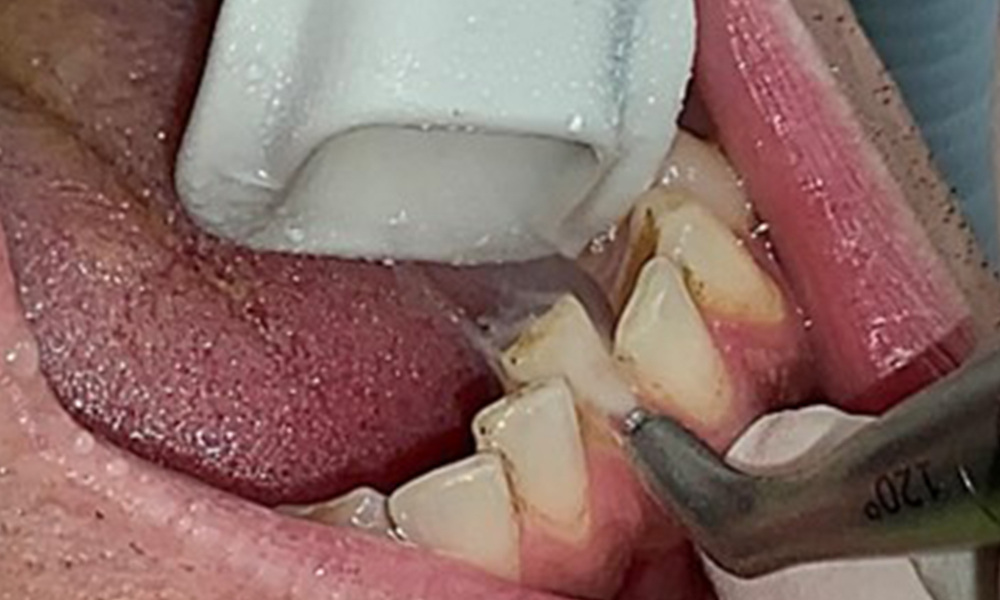

Anwendung der Interdentalbürstchen in Rg 44/45

Abb. 9: Anwendung der Interdentalbürstchen in Rg 44/45, © Dr. R. Krapf

Zugleich ist es notwendig die Interdentalraumbürstchen, welche der

Patient täglich verwendet nach der richtigen Größe zu überprüfen und den Patienten zu bestärken diese konsequent zu benutzen (Abb. 9). Eine

gute Mundhygiene ist unabdingbar, um das Parodontitisrisiko durch das Rauchen zu minimieren.